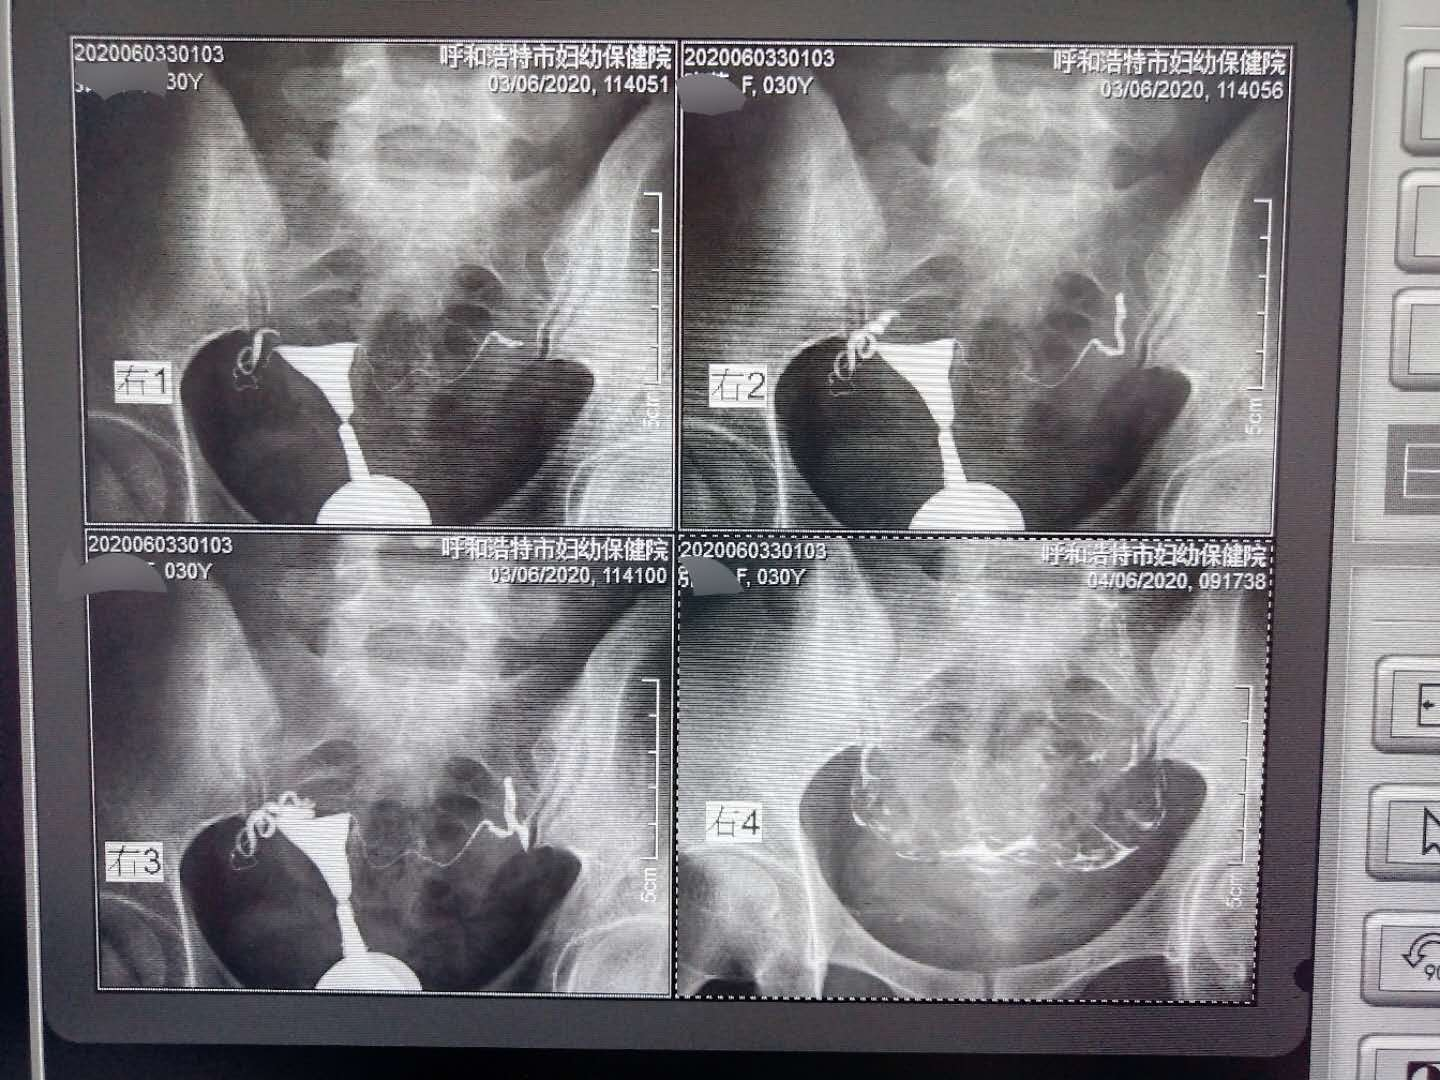

子宮輸卵管造影在呼市婦幼保健院影像科已有20多年臨床經(jīng)驗,為不孕不育患者提供了準(zhǔn)確的診斷與治療,已讓很多患者受益。子宮輸卵管造影經(jīng)宮頸口注入造影劑,使子宮和輸卵管內(nèi)腔顯影,了解宮腔位置、大小、形態(tài)、有無畸形及輸卵管是否通暢等的X檢查方法。